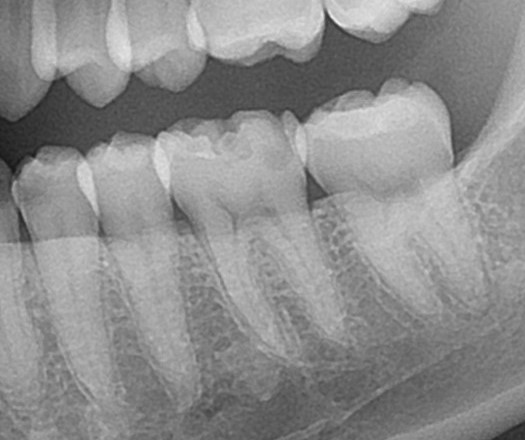

エックス線写真を見てみると

見えない歯の中が見えてきます。

虫歯は歯が溶けてしまう病気で、歯が溶けると、レントゲン写真では黒い影が出てきます。

虫歯の黒い影はここにあります。